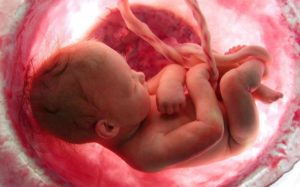

- Будущий малыш уже набрал от 1100 до 1300 г и вырос до 36 — 37 см, окружность его головы — 24-28 см. В этот период идет интенсивное развитие ткани мышц.

Длина тела плода составляет около 37 сантиметром, он весит больше килограмма.

У него есть полный набор органов и тканей, которые сформировались и теперь будут только расти и совершенствоваться.

Организм ребенка на 28 неделе беременности уже достигает массы тела более 1 килограмма, а длина тела уже превышает 37 см.

Малыш постепенно накапливает подкожно-жировую клетчатку, и поверхность тела покрыта специальной смазкой, которая облегчает движения малыша в полости матки.

Внешний вид плода:

- Ребенок резко поправляется и его вес достигает 1-1,3 кг;

- Рост малыша становится 35-37 см;

- Ресницы малыша удлиняются и становятся более объемными;

- Кожа становится более гладкой и нежной (причина — возрастание объема подкожной клетчатки);

- Ногти на руках и ногах продолжают расти;

- Волосики на голове ребеночка становятся длиннее;

- Волос малыша приобретает индивидуальную окраску (начинает активно вырабатываться пигмент);

- Лицо и тело покрываются защитной смазкой.